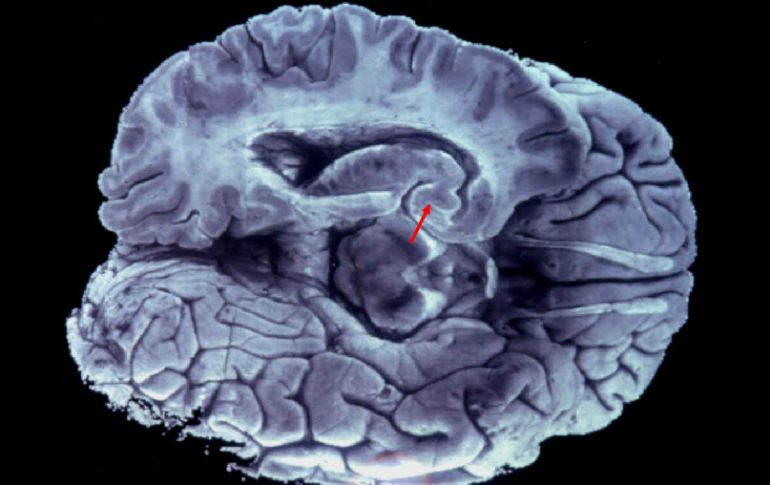

Tecnología | La aplicación directa del sistema estimula las áreas del cerebro dañadas Terapia con electrodos, acelera recuperación tras parálisis cerebral La aplicación directa del sistema estimula las áreas del cerebro dañadas Por: EFE 26 de marzo de 2016 - 21:04 hs La terapia debe hacerse de forma constante en la cabeza del paciente a niveles muy bajos. EFE / ARCHIVO WASHINGTON, ESTADOS UNIDOS (26/MAR/2016).- La aplicación directa de un sistema de electrodos podría acelerar la recuperación de las personas con parálisis cerebral, según un estudio que publica hoy la revista Science Translational Medicine. La aplicación de una corriente eléctrica en el cuero cabelludo para estimular las áreas del cerebro dañadas podría ayudar a las personas que han sufrido un derrame cerebral, según este nuevo estudio de la Universidad de Oxford (Reino Unido). La investigación, liderada por la profesora Heidi Johansen-Berg, y el doctor Charlotte Stagg, del departamento de neurociencia clínica de Oxford, analizó el uso de la corrientes transcraneales de estimulación directa (tDCS, por sus siglas en inglés). La aplicación se hace de forma constante en la cabeza del paciente, aunque a niveles muy bajos de corriente eléctrica, según explican los científicos. "Para los pacientes con parálisis cerebral, una rehabilitación más extensa e intensa, les lleva a una gran recuperación", señaló Johansen-Berg. Veinticuatro voluntarios con parálisis cerebral participaron en el estudio, todos ellos con afectaciones en las extremidades superiores. Los pacientes se dividieron en dos grupos para recibir diferente rehabilitación motora: mientras en un grupo se implementó el tratamiento pionero conocido como tDCSm, el otro grupo siguió el tratamiento a base de los electrodos tradicionales. Después de tres meses de rehabilitación, el grupo que registró una reacción más favorable a las medidas clínicas fue el expuesto al tratamiento experimental, en comparación con el grupo de control. "Los pacientes que recibieron el tratamiento de tDCS podían mover mejor las manos y los brazos, con movimientos como levantar las extremidades, estirarse para alcanzar o agarrar objetos", explicó Johansen-Berg. Los límites del tratamiento son ahora de presupuesto y logísticos: "los costes y la disponibilidad de personal", señaló la investigadora. Sin embargo, el equipo de Oxford confía en que la implementación del nuevo tratamiento avance con el tiempo. Temas Estudios científicos Ciencia médica Cerebro Calor de hogar Salud general Lee También Julieta Fierro será homenajeada en la FIL Inapam: Así puedes acceder a consultas médicas GRATIS con la credencial INAPAM: ¿Cómo solicitar un turno para consulta médica gratuita? Sheinbaum defiende el impuesto a bebidas azucaradas Recibe las últimas noticias en tu e-mail Todo lo que necesitas saber para comenzar tu día Registrarse implica aceptar los Términos y Condiciones